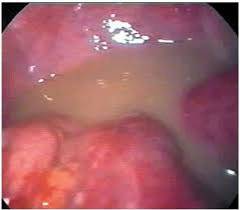

При этом заболевании наблюдаются обильные, густые творожистые выделения с кислым запахом, прилипшие к стенкам влагалища. У женщин возникают зуд, жжение и раздражение, усиливающиеся после полового акта или теплых водных процедур. На слизистой влагалища и его входе отмечаются покраснение и отек.

Хронический кандидозный кольпит (вагинит)

Это состояние развивается при длительном течении болезни более двух месяцев. Симптомы не ярко выражены, но могут усиливаться под воздействием провоцирующих факторов, таких как предменструальный период, беременность или переохлаждение.